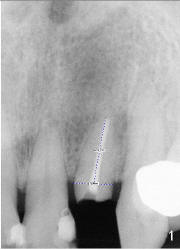

The tooth #7 was fractured in a 67-year-old lady (Fig.1).  Treatment plan is extraction of the affected tooth and placement of immediate implant.  The question is how to close the extraction socket with a proper sized implant without exposure of implant threads (rough surface).